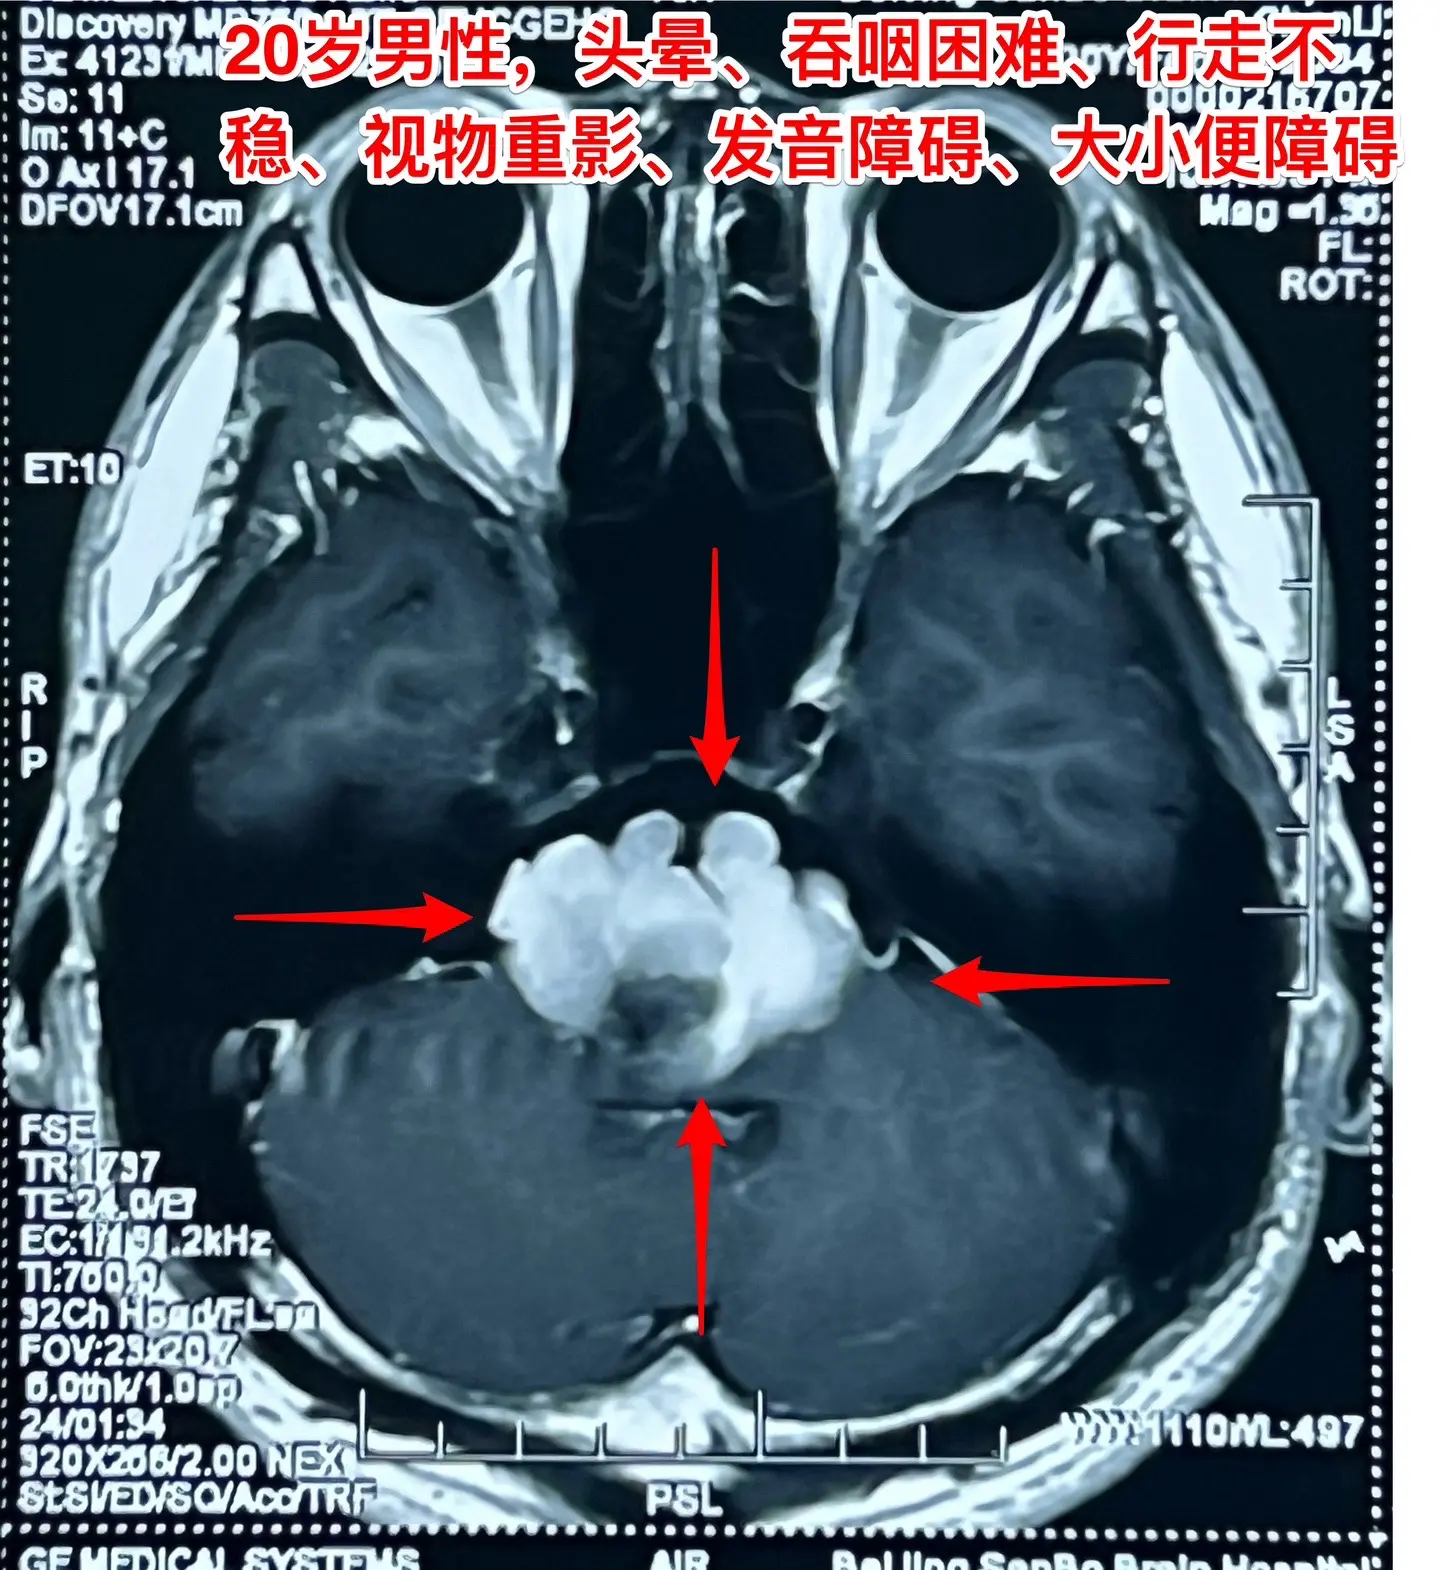

头晕、吞咽困难、行走不稳、大小便障碍。20岁漳州的小伙子,2个月前出现头晕,一个月前出现吞咽困难,半个月个月前出现多睡,一周前出现行走不稳、视物重影、发音不清晰,而且有大小便障碍。 一般人认为这些症状都是七八十岁的老人才会有的,怎么会出现在20岁的年轻人身上呢?他到底得了什么病? 磁共振和CT显示脑干腹侧有一个巨大囊肿,对脑干有明显的压迫,考虑为肠源性囊肿。针对这个病,只有选择作手术切除囊肿,病人的症状才有希望好转。 2024.8.14作了手术,术中看见囊壁与脑干的神经、基底动脉的分支血管粘连。切除大部分囊壁,清除了囊内容物,脑干得到充分减压。 手术后病人的症状显著改善了!